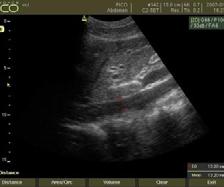

Stabilirea indicaţiei tratamentului endovascular cu DEBDOX necesită o pre-evaluare CT (“triple-phase”) sau IRM cu contrast, coroborată cu manifestările clinice și a datelor de laborator (AFPdeterminare cantitativă folosită ulterior în dinamica pentru evaluare, follow-up). Fiecare flacon de microsfere va fi încărcat cu 50-75 mg de Doxorubicin (doza de încărcare 25-37,5 mg Doxorubicin/ ml de microsfere)

• Ablația tumorală hepatică cu microunde (MWA) utilizează căldura din energia microundelor pentru a distruge celulele canceroase hepatice. Pentru a realiza procedura, este introdus pe cale percutană un ac în tumora hepatică, sub ghidaj imagistic, ecografic sau CT. Se știe că celulele maligne sunt mai sensibile la leziunile prin hipertermie decât celulele normale , ca urmare creșterea temperaturii intatumorale prin curentii MWA vor distruge tumora.